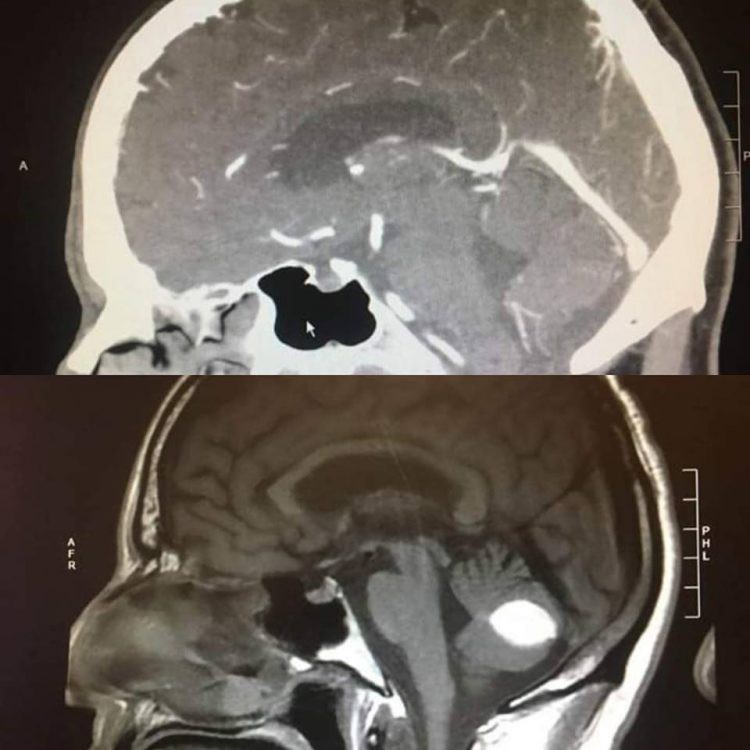

Trời đất như sụp đổ trước mắt ông Paul khi bác sĩ giải phẫu thần kinh tại bệnh viện UC San Francisco thông báo một tin sét đánh rằng ông đã bị chảy máu não. Rồi kết quả chụp X-quang lại cho thấy ông Paul có một khối u trong não. Cả 2 kết quả đều không phải là tin tốt lành đối với Paul vì ông buộc phải làm phẫu thuật gấp để tránh nguy hiểm đến tính mạng và để lại hậu họa về sau.

Thế rồi, trước ngày lên bàn mổ 1 ngày, ông Paul đến bệnh viện để chụp cắt lớp lần nữa thì bác sĩ phát hiện ra khối u đã tự nhiên biến mất, não của Paul hoàn toàn bình thường. Trong khi các bác sĩ bối rối không hiểu chuyện gì đang xảy ra với người đàn ông này thì ông Paul cho rằng đó là phước lành mà Chúa đã ban cho ông. Paul coi đó là điều kỳ diệu.

Sau đó bác sĩ đề nghị Paul hợp tác để tiếp tục nghiên cứu xem tại sao lại có chuyện hoang đường như vậy xảy ra. Tấm phim chụp vẫn còn đó, đốm trắng trong não Paul là hoàn toàn có thật nhưng không ai hiểu tại sao nó lại biến mất bí ẩn như vậy.